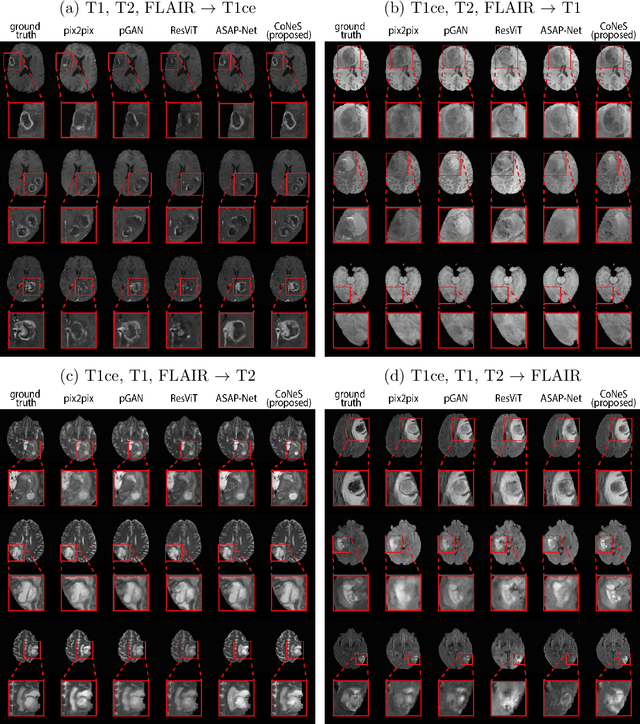

Abstract:Multi-sequence magnetic resonance imaging (MRI) has found wide applications in both modern clinical studies and deep learning research. However, in clinical practice, it frequently occurs that one or more of the MRI sequences are missing due to different image acquisition protocols or contrast agent contraindications of patients, limiting the utilization of deep learning models trained on multi-sequence data. One promising approach is to leverage generative models to synthesize the missing sequences, which can serve as a surrogate acquisition. State-of-the-art methods tackling this problem are based on convolutional neural networks (CNN) which usually suffer from spectral biases, resulting in poor reconstruction of high-frequency fine details. In this paper, we propose Conditional Neural fields with Shift modulation (CoNeS), a model that takes voxel coordinates as input and learns a representation of the target images for multi-sequence MRI translation. The proposed model uses a multi-layer perceptron (MLP) instead of a CNN as the decoder for pixel-to-pixel mapping. Hence, each target image is represented as a neural field that is conditioned on the source image via shift modulation with a learned latent code. Experiments on BraTS 2018 and an in-house clinical dataset of vestibular schwannoma patients showed that the proposed method outperformed state-of-the-art methods for multi-sequence MRI translation both visually and quantitatively. Moreover, we conducted spectral analysis, showing that CoNeS was able to overcome the spectral bias issue common in conventional CNN models. To further evaluate the usage of synthesized images in clinical downstream tasks, we tested a segmentation network using the synthesized images at inference.